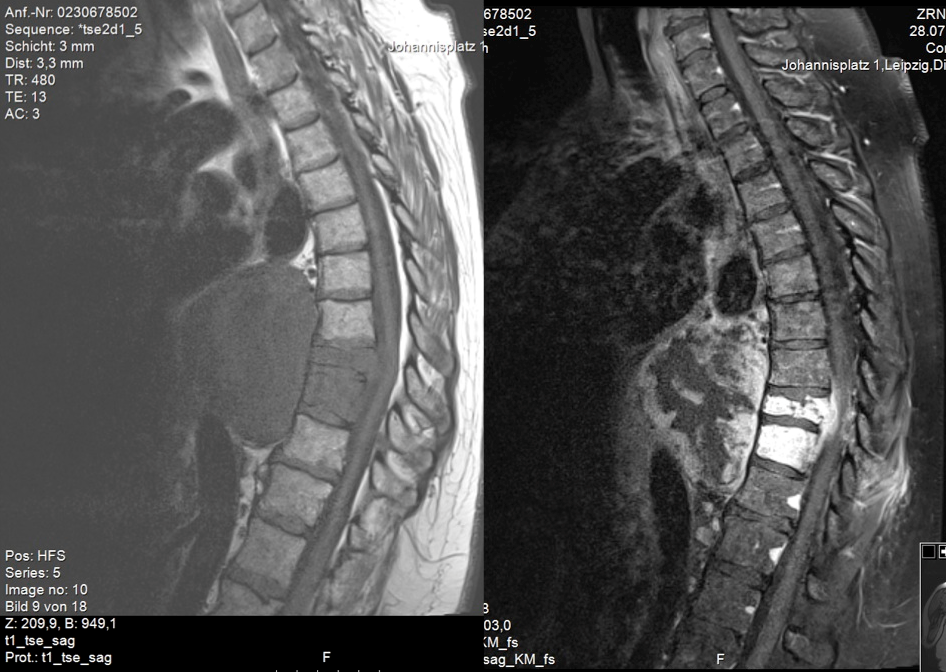

A 59-year-old woman presented with persistent pain in the thoracic spine after low energy trauma 6 weeks ago. X-ray imaging showed vertebra compression fracture of Th9 with kyphosis of 20°. The patient had a history of three strokes, 15 and 13 years ago, with residual paralysis on the right side. She did not report of new neurological disability after trauma: no new motor dysfunction, no long tract signs, neither bladder nor bowel dysfunction. There was no history of malignancy in her family. MRI studies revealed a solid mass of 16x14x12 cm in the inferior posterior mediastinum on the left side with infiltration of Th9 and Th10 vertebral body and spinal canal infiltration with myelon compression (Figure 1 [Fig. 1], Figure 2 [Fig. 2]). Staging procedure including total spine MRI, abdominal and chest computed tomography (CT), cranial CT, and PET CT did not show distant metastasis. The interdisciplinary tumor board decided to perform a transthoracic needle aspiration biopsy first. The histopathological examination could not define a clear diagnosis. Therefore an open biopsy was performed. This result was not clear, too. At last, pleomorphic rhabdomyosarcoma or liposarcoma with rhabdomyogenic dedifferentiation were discussed. The proliferation index Ki67 was 70%, meaning high-grade sarcoma. Trimodality treatment was proposed: surgery with “en-bloc” resection followed by adjuvant multidrug chemotherapy and radiation beam therapy. The day after biopsy, the patient suddenly developed an ascending sensory spinal cord injury. We decided for a two-stage surgery, starting with immediate posterior decompression and stabilization: We performed a posterior decompression with complete resection of the posterior parts of the Th9 and Th10 vertebra with spinal canal clearance. Long segment stabilization was performed three levels above and three levels below (Figure 3 [Fig. 3]). After a few days of recovery the anterior procedure followed (Figure 4 [Fig. 4]). Via thoracolumbophrenotomy an “en bloc” resection including TH9 and Th10 vertebral body as well as 2 level cage reconstruction of the anterior column was performed (Figure 5 [Fig. 5], Figure 6 [Fig. 6]). The patient recovered quite well after surgery: no problems of wound healing, no new neurological deficits, sensory deficit improved. Adjuvant chemotherapy started 4 weeks after surgery with the first of 3 cycles in a 21 days period. Unfortunately chemotherapy had to be reduced and later stopped due to major side effects. A radiation beam therapy with total radiation dose of 60 Gy followed. The patient did well at 3 month and 6 month follow-up, showing no new neurological deficits, less pain. MR imaging after 6 month did not show local recurrence and PET CT did show no proof of relapse.

Figure 1: Sagittal MR image of the thoracic spine. Left: T1-weighted image. The tumor represents as a hypointense mass infiltrating the spine with spinal canal penetration. Right: T1-weighted, contrast enhanced image. Inhomogeneous gadolinium distribution.